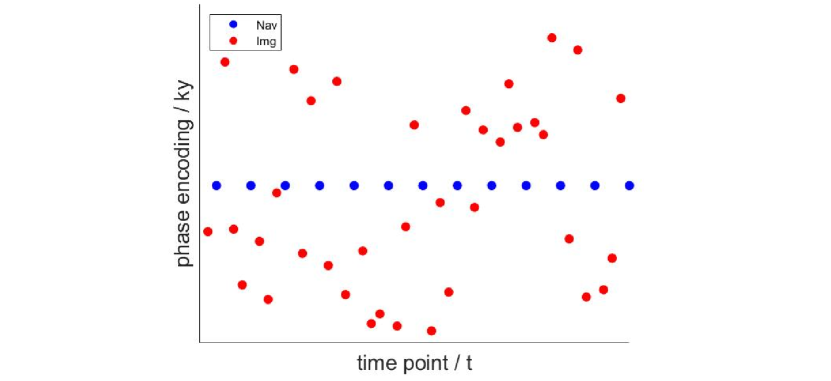

The data acquisition of PS model is divided into two parts, as illustrated in Figure 1. “Navigating data” samples the center region of k-space at high temporal resolution, while “Imaging data” slowly samples the whole k-space. The two parts of data are sampled in an interleaved fashion. A two-step framework is adopted for image reconstruction. First, singular value decomposition (SVD) is performed on and the first singular vectors are extracted as . Second, is assumed to be fixed, is calculated by minimizing the noise energy:

Simulation data were generated by the following steps. First, the dynamic k-space data was interpolated to a given temporal resolution, which was set to be approximately 12 ms in this paper, in order to be consistent with the settings used for in-vivo data acquisition. Second, the raw data of one cardiac cycle was repeatedly extended to a given total length. In order to avoid complete periodicity of the simulated data, we performed random interpolation along the time dimension among cardiac cycles to simulate the variable heart beats. Third, each data was undersampled according to the interleaved sampling pattern as shown in Figure 1. The generated data was used for the following reconstruction experiments.